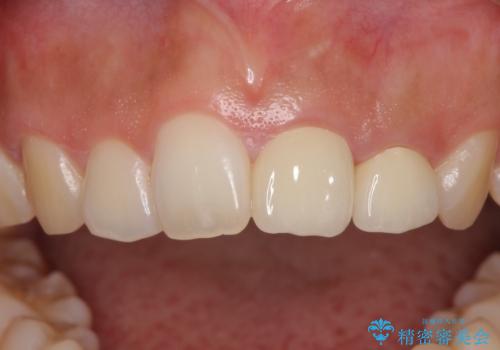

仮歯装着の時点で自然な見た目となり、オールセラミッククラウンを装着した際には、まるで自分の歯のようと喜んでくださいました。

長年変色を気にしており、もっと早くに治療を行えば良かったとおっしゃっていました。